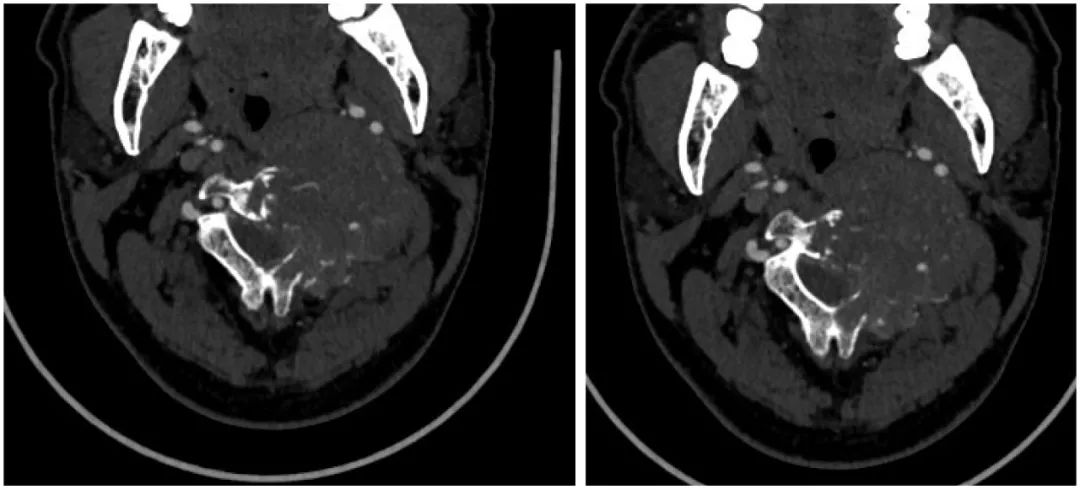

病史:male, 63 y/o

Neck pain for 3 months

影像资料:

诊断:C2椎体肿瘤